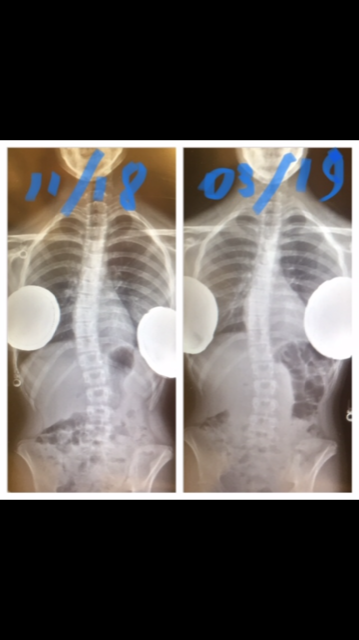

OUR PATIENT GALLERY